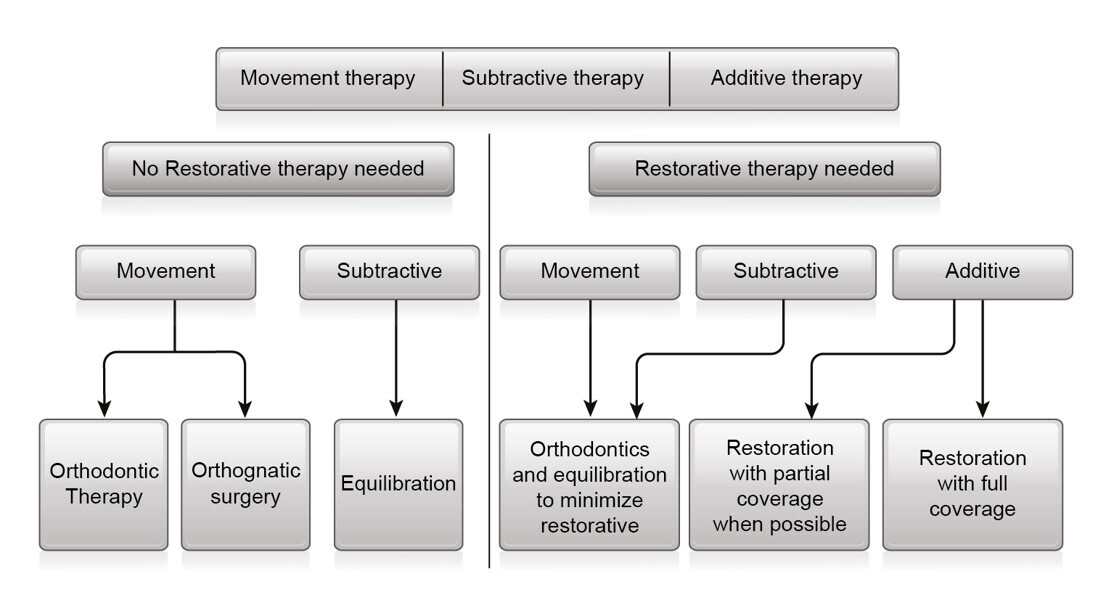

Fig. 17: Treatment modalities to recreate intercuspation in the new mandibular position.